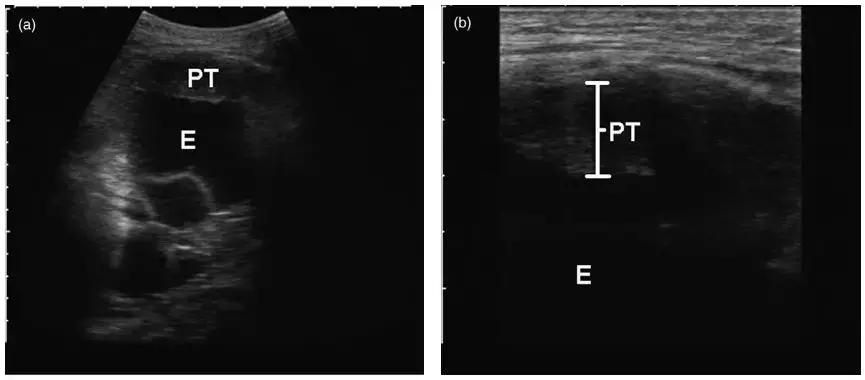

三、彩超引导下胸膜活检

超声指引下,切割活检针达到目标部位后扣动弹簧扳机完成活检,所以特异性和敏感性都不错。

这是在彩超引导下的胸膜活检,胸水较少,胸膜局灶增厚。在穿刺中,可以看到针的所在位置。

优点:实时引导、无射线暴露、费用相对较低。